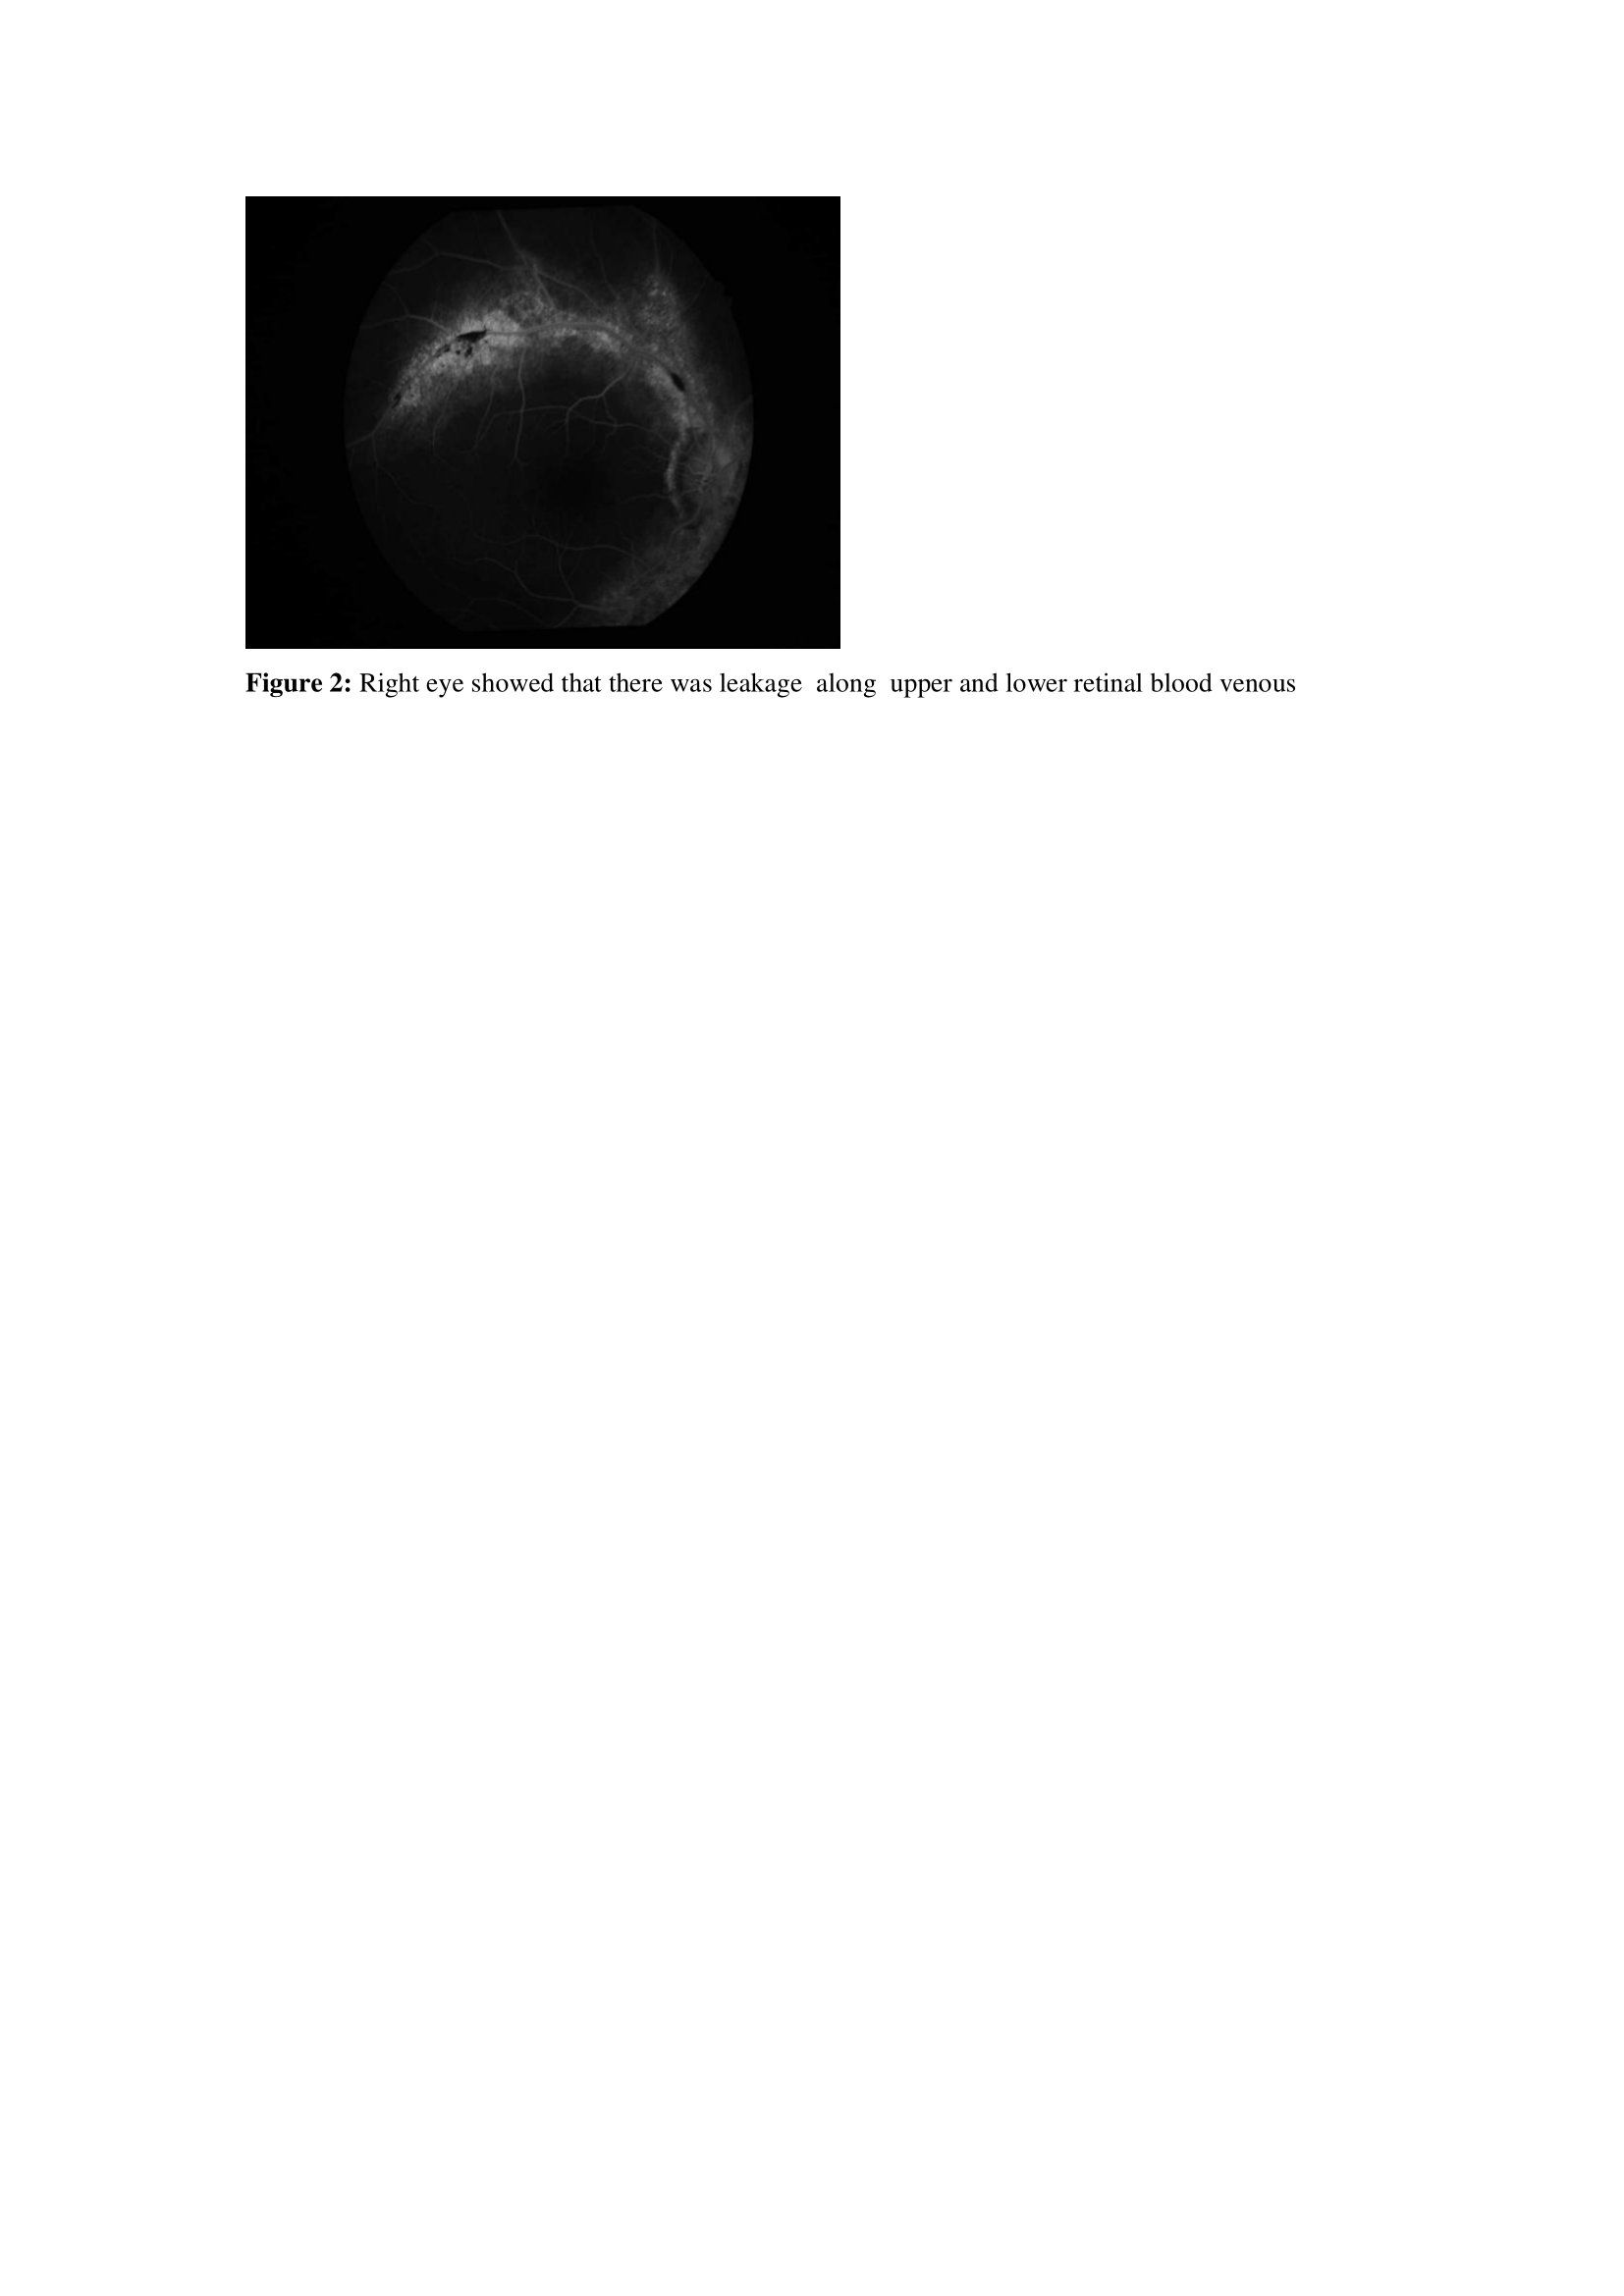

Fundus fluorescein angiography during admission showed that there was Central retinal whitening with no cotton wool spots .there was no Obstruction of microcirculatory blood flow with normal perfusion of retinal blood flow, as shown in (figures 1 and 2) for the right eye and (figures 3 and 4) for the left eye.